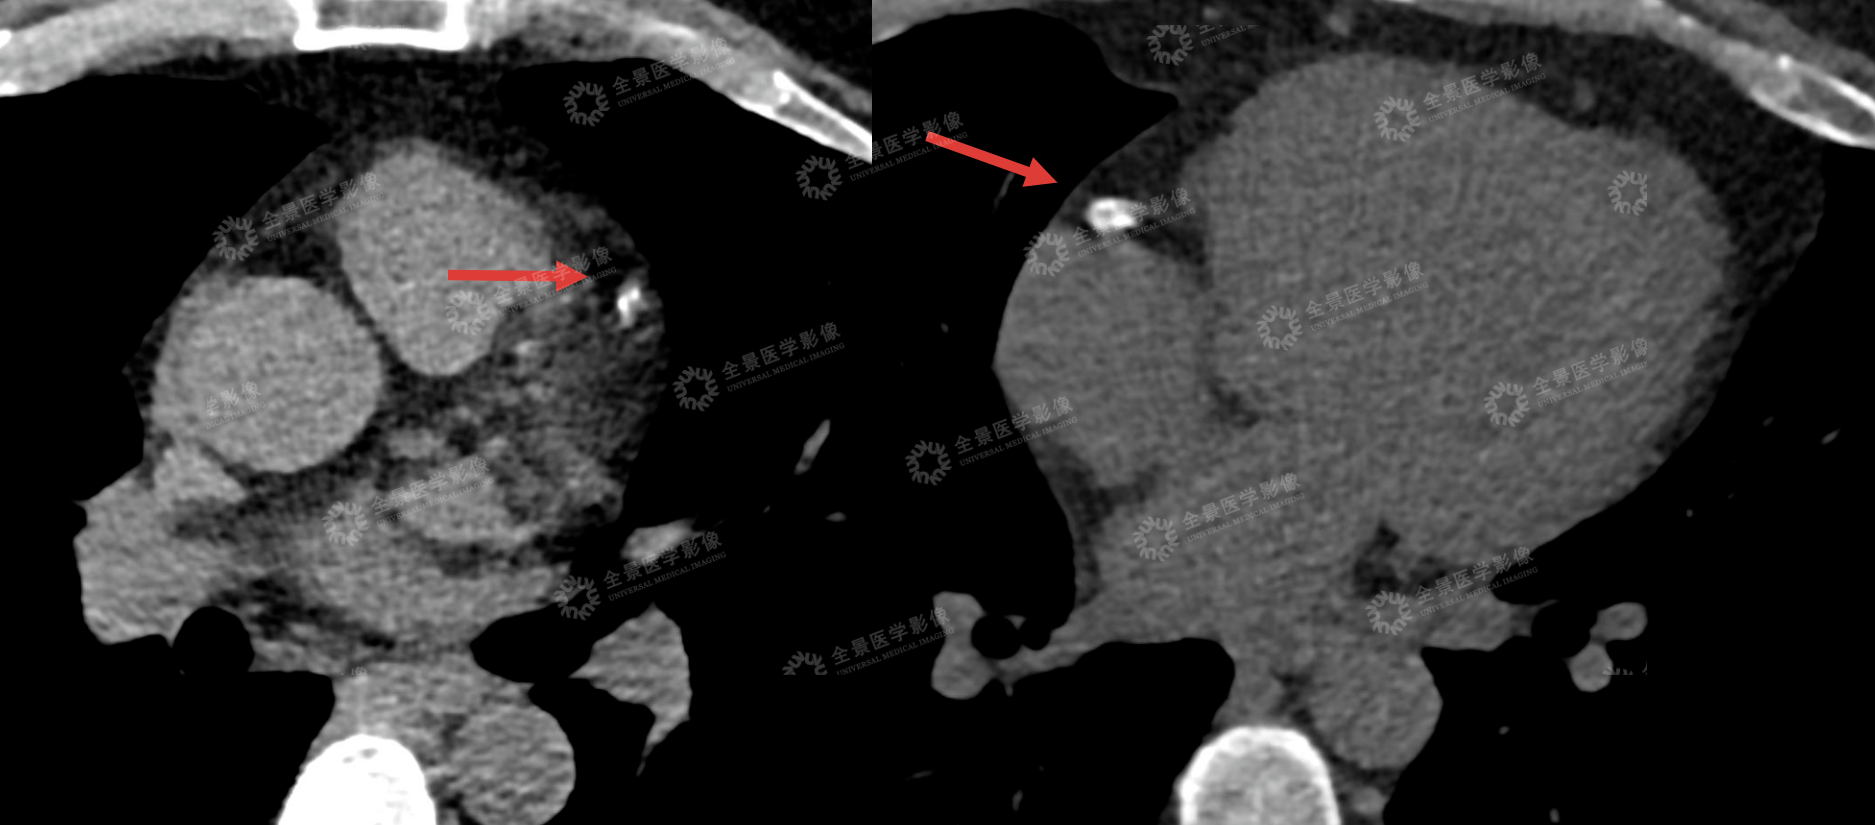

冠脉 CTA 、头颅血管成像(MRA)影像提示:心脏有易破裂「不稳定斑块」,并且管腔已 90%-100% 闭塞,对角支也有钙化斑块,同时脑血管也有问题:右侧大脑中动脉变细,远端几乎看不清....

心脏血管危机:左前降支(LAD,被称为 「心脏生命线」)近中段及对角支 D2 起始段,同时存在钙化与非钙化斑块 —— 其中 LAD 中段的 「非钙化斑块」 属于不稳定斑块(易破裂形成血栓),且管腔 90-100% 闭塞(相当于血管几乎堵死,随时可能突发心梗)。